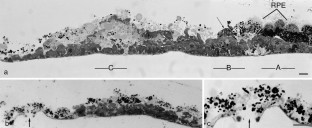

A 78-year-old woman with AFVD underwent MT with 360° retinotomy 3–4 months after loss of reading ability. Most of the vitelliform material was lost during surgery; the subfoveal tissue was excised, fixed in aldehydes, postfixed in reduced OsO4 and embedded in epoxy resin. Semithin sections were stained with toluidine blue for light microscopy (LM) and thin sections with uranyl acetate and lead citrate for transmission electron microscopy (TEM).

Postoperatively, the patient developed a retinal detachment complicated by proliferative vitreoretinopathy (PVR) requiring two additional vitreoretinal procedures before finally the silicone oil could be removed. Twenty-two months after MT the distance visual acuity was unchanged at 0.2; the near visual acuity had improved from less than 0.1 before MT to 0.4. The retina was completely attached. LM and TEM revealed serious alterations indicative of a breakdown of the outer layer of the retina.

Through the present single case it is not possible to determine whether MT could be a therapeutic approach in patients with AFVD. The most important cause for the limited postoperative visual improvement seems to be a primary injury of the foveal function due to the AFVD. This is supported by the extensive subfoveal degeneration and necrosis affecting not only the RPE cells but also their basement membrane and the interposed basal laminar deposits.